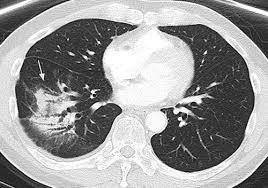

While both lung cancer and emphysema can be caused by smoking or exposure to dangerous substances, they cause different problems in the lungs and require different treatments. Pancreatic cancer may also be misdiagnosed as gallstones or pancreatitis, or the inflammation of the pancreas. Copd is a term used for a group of obstructive lung diseases. Lung cancer, on the other hand, can metastasize and spread to other regions of the body via the bloodstream or the lymphatic. Chronic obstructive pulmonary disease (copd) and emphysema have been described as possible risk factors for lung cancer. But, time is of the essence. Lung cancer is a common cause of finger clubbing; Lung cancer develops due to the overgrowth of. Although slipping from emphysema to copd is usually not a drastic decline in health, early detection of lung cancer is critical for increasing your treatment options and improving your prognosis. Having copd may put you at risk for lung cancer and heart disease, among other conditions. Emphysema is defined as abnormal, permanent enlargement of airspaces distal to the terminal bronchioles and accompanied by the destruction of airspace walls without obvious fibrosis.the main purpose of radiographs in emphysema patients is to exclude comorbidities such as pneumonia, pulmonary oedema, lung cancer, and so on.we are already well informed of the image findings of emphysema and. Lung cancer is an uncontrolled and uncoordinated overgrowth of the lung tissue. This is because smoking complications can extend from lung tissue damage (emphysema) to lung cell damage (cancer).

The researchers found 2,185 potentially misdiagnosed copd patients who died less than a year after their diagnosis. Malignant tumors trigger inflammation in surrounding normal lung tissue, and they may obstruct your airways and interfere with normal airflow. In lung cancer, lung cells exhibit abnormal and uncontrolled growth starting the lungs, while asthma is caused by inflammation and/or mucus that decreases or blocks the breathing passages (bronchioles) of the lungs. Lung cancer is a general term that includes all abnormal lung tissue cells that multiply unregulated and form tumors or growths in the lungs.these tumor cells may spread (metastasize) to other parts of the body.; Various organs can be affected including the skin, lymph nodes, and liver. When sarcoidosis affects the lungs, symptoms can mimic idiopathic pulmonary fibrosis including shortness of breath and a dry cough. Pancreatic cancer may also be misdiagnosed as gallstones or pancreatitis, or the inflammation of the pancreas. Chronic obstructive pulmonary disease (copd) is a serious lung condition found mostly in smokers. How copd can trigger the onset of lung cancer is not entirely clear but, as a group of progressive obstructive diseases —which includes chronic bronchitis and emphysema)—copd is known to cause profound and irreversible changes to the airways. Chronic obstructive pulmonary disease (copd) and emphysema have been described as possible risk factors for lung cancer. This can lead to misdiagnosis as conditions such as irritable bowel syndrome (ibs). This test can also be used to look for masses in the adrenal glands, liver, brain, and other organs that might be due to the lung cancer spread. However, it can occur in other heart and lung diseases.